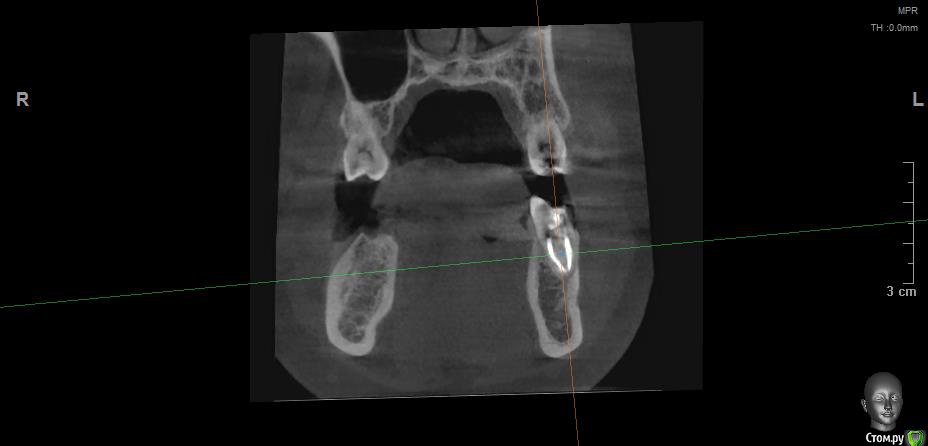

Vords Опубликовано 11 июня, 2020 Поделиться Опубликовано 11 июня, 2020 (изменено) Доброго вечера, профессионалы. Прошу у Вас помощи. Буду очень благодарен за консультацию. 3 недели назад появились боли в в жевательных зубах (около 37 и 36 зубов). В виду того, что боли были достаточно серьезные, а врач, у которого я лечился ранее не мог меня принять из-за пандемии - пришлось идти в городскую поликлинику. По результатам похода был поставлен диагноз пульпит 37 и глубокий кариес 36. На 36 поставили пломбу - 37 успешно депульпировали. На этом история 37 зуба закончена. С 36 после постановки пломбы начались дикие ночные боли и боли при накусывании. На повторном приеме был поставлен диагноз пульпит 36 - поставлено лекарство для умертвления нерва. После этого боль при накусывании прошли. В следующий прием пришел на чистку каналов и пломбировку. Во время этой процедуры я вдруг ощутил совершенно дикую боль (как выяснилось потом - в этот момент и произошла перфорации в области фуркации). Врач ничего не сказал - просто поставил метапекс и запломбировал каналы. В этот момент начались боли при накусывании. а потом постоянная тянущая боль. Продолжалось это около 3 дней - я пошел в другую стоматологию где мне сделали рентген и с подозрение на перфорацию отправили на КТ. По результатам КТ перфорация была подтверждена. С КТ я пришел в городскую стомотологию где мне предложили закрыть перфорацию цементом (pro что-то там - не могу сказать точно). Закрыли ее во вторник на этой неделе. Сегодня восстановили коронку и поставили световую пломбу. Беда в том, что боль при накусывании и "нытье" с этой стороны так и не прошли. По словам стомотолага гос клиники - боль при накусывании из-за метапекса и когда он рассосется - боль пройдет. (до 6 месяцев). Я прилагаю рентген (ужасное качество), фото КТ и ссылку в облако на КТ. Я допускаю, что никто не захочет лезть в облако и тратить свое время на просмотр на КТ (сам не могу разобраться с программой, что бы сделать достойные скрины), но если вдруг у кого-то найдется время - буду очень благодарен. Рентген сделан сразу после пломбировки канала. КТ через 3 дня после этого. В связи с этим вопрос. Возможно ли, что боль при надавливании пройдет если подождать пока рассосется метапекс или это пустая трата времени? Мне стоит ждать какое - то время или в этой ситуации мне поможет только удаление? Благодарю Вас за уделенное время Ссылка на КТ https://cloud.mail.ru/public/44WE/2JeTfXmr2 Изменено 11 июня, 2020 пользователем Vords Ссылка на комментарий

krokomot Опубликовано 11 июня, 2020 Поделиться Опубликовано 11 июня, 2020 Судя по всему у вас в 6м зубе выведен не только метапекс но и гуттаперчевый штифт, скорее всего, если это не исправить боли сохранятся, и что там с коронкой не понятно, на кт сильные тени из-за большого объема рентгеноконтрасного материалла, а прицельный снимок что вы сделали, сделан не поп правилам и на нем сильные искажения, понять трудно что с коронкой. Короче, зуб с перфорацией , выведенным материалом за апексом и гуттаперчей, и при этом еще и беспокоит, прогноз сомнительный. возможно всё можно переделать и всё станет нормально , но это не точно. Вам нужен грамотный доктор эндодонтист. 1 Ссылка на комментарий

wladdX Опубликовано 11 июня, 2020 Поделиться Опубликовано 11 июня, 2020 (изменено) Скриншоты Изменено 11 июня, 2020 пользователем wladdX 1 Ссылка на комментарий

Vords Опубликовано 11 июня, 2020 Автор Поделиться Опубликовано 11 июня, 2020 (изменено) WladdX, огромное спасибо Вам за потраченное на скрины время. А то я так и не смог освоить эту программу (рукалицо). У меня даже есть ощущение, что я вижу теперь штифт, о котором говорил krokomot (хотя и не факт)))) Изменено 11 июня, 2020 пользователем Vords Ссылка на комментарий